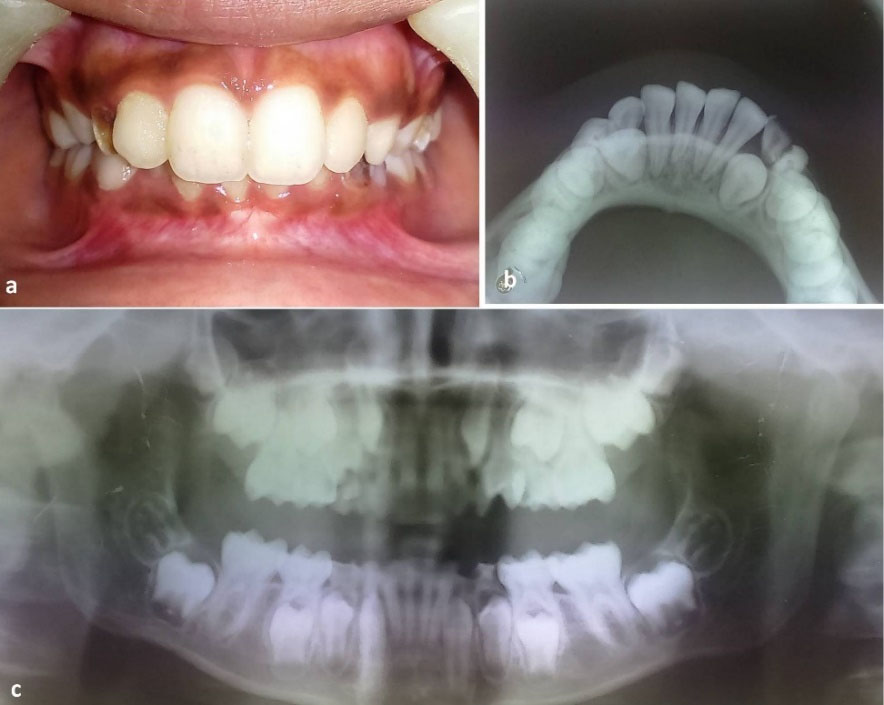

Figure 3.

Postoperative occlusion after the removal of the splint (a). Mandibular occlusal radiograph (b) and panoramic radiograph (c) showing bone healing at the fracture site.